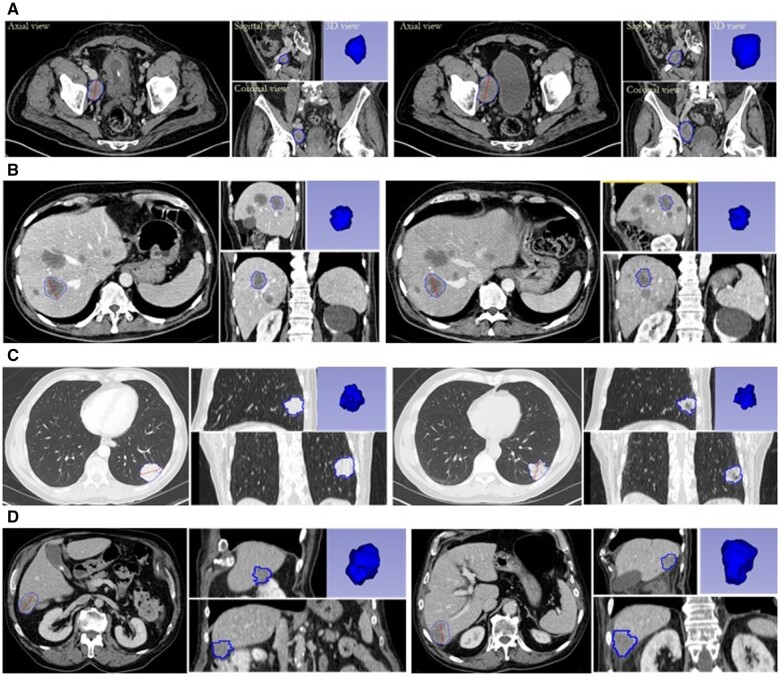

Materials and methods: Target lesions in lung, liver, and lymph nodes were randomly chosen from patients in 10 historical clinical trials for various cancers, ensuring a balanced representation of lesion types, diameter ranges described in the QIBA Profile, and variations in change magnitudes. Three radiologists independently segmented these lesions at baseline and follow-up scans using 2 software tools. Two types of predefined disagreements were assessed: Type I: substantive disagreement, where the disagreement between QIBA CTvol classifications and RECIST categories could not be attributed to the improved sensitivity of volumetry in detecting changes; and Type II: disagreement potentially arising from the improved sensitivity of volumetry in detecting changes. The proportion of lesions with disagreements between QIBA CTvol and RECIST, as well as the type of disagreements, was reported along with 95% CIs, both overall and within subgroups representing various factors.

Results: A total of 2390 measurements from 478 lesions (158 lungs, 170 livers, 150 lymph nodes) in 281 patients were included. QIBA CTvol agreed with RECIST in 66.6% of interpretations. Of the 33.4% of interpretations with discrepancies, substantive disagreement (Type I) occurred in only 1.5% (95% CI: [0.8%, 2.1%]). Factors such as scanner vendor (P = .584), segmentation tool (P = .331), and lesion type (P = .492) were not significant predictors of disagreement. Significantly more disagreements were observed for larger lesions (≥50 mm, as defined in the QIBA Profile).